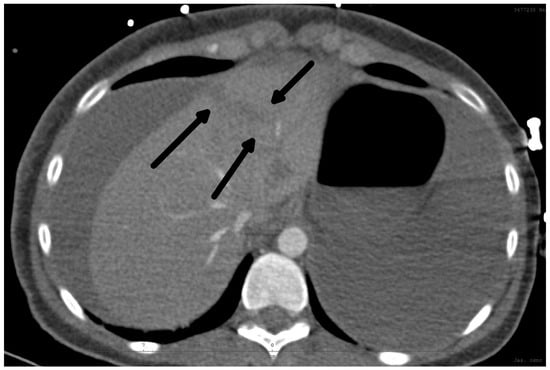

The diagnosis of liver injury was made by clinical and paraclinical examination and confirmed by imaging techniques. (computed tomography (CT) or ultrasound) (Table 2) (Figure 1 and Figure 2).

Figure 2.

CT scan: Rupture of the liver along falciform ligament (arrows) and hemoperitoneum frontal view.